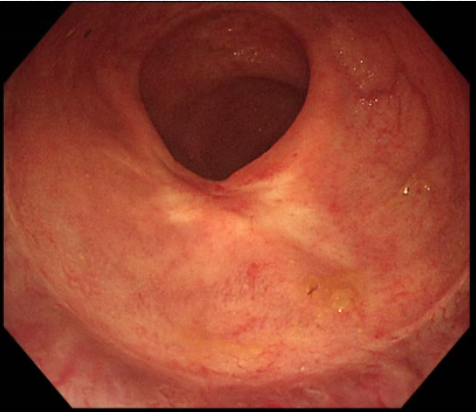

第二次复查,仅残留细小溃疡面

第三次复查溃疡基本愈合

付出终有回报。经过数个周期的系统治疗,7月4日,肛肠科为刘爷爷肛诊时发现肿瘤已明显缩小、软化,甚至不易触及。9月25日,复查肠镜及病理显示原直肠肿瘤处仅见纤维组织增生和炎细胞浸润,未见明确肿瘤残留。乙状结肠的息肉也通过内镜下手术(CSP)顺利切除。